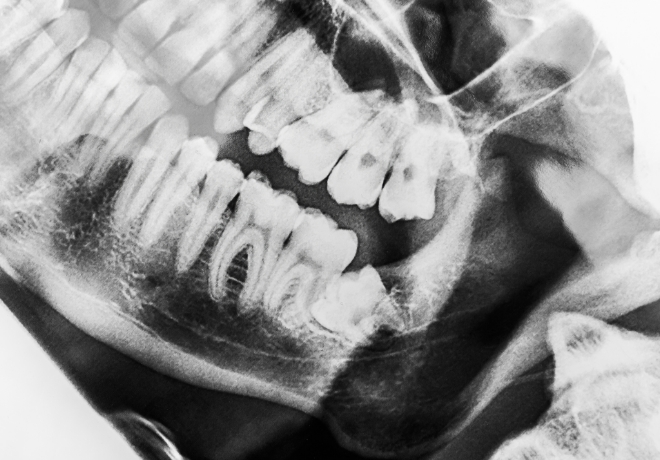

根の治療について

歯の神経や血管など(歯髄)が通っている根っこのような部分を根管(コンカン)といいます。進行した虫歯などで根管が炎症や感染を起こした時に、そのまま放置してしまうことで、強い痛みが出たり歯ぐきが腫れたり、場合によっては、リンパを通じて全身に症状(発熱・怠さなど)がでる場合があります。

根管治療は、根管の掃除・除痛を行う治療です。歯髄を除去し、根管を清潔にし、代わりに防腐剤で詰め物をすることで、感染等を防ぐ治療目的で行います。